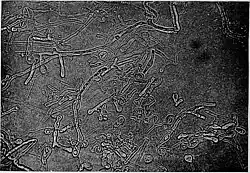

Blastomyces is a genus of fungi in the order Onygenales. Species are known human pathogens and show thermal dimorphism, converting from hyphal states under saprobic conditions to yeast-like states under pathogenic conditions. They are the causative agents of blastomycosis, a systemic mycosis in immunocompromised patients.[1][2]